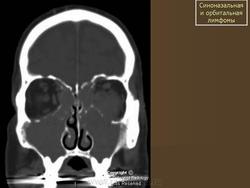

Диагноз злокачественной лимфомы орбиты труден. Из инструментальных методов исследования более информативны ультразвуковое сканирование, компьютерная томография (рис. 20.24, в) и тонкоигольная аспирационная биопсия с цитологическим исследованием. Необходимо обследование у гематолога для исключения системного поражения. Наружное облучение орбиты — практически безальтернативный высокоэффективный метод лечения. Полихимиотерапию подключают при системном поражении. Эффект лечения проявляется в регрессии симптомов патологического процеса в орбите и восстановлении утраченного зрения. Прогноз при первичной злокачественной лимфоме для жизни и зрения благоприятный (83 % больных переживают 5-летний период). Прогноз для жизни резко ухудшается при диссеминированных формах, но частота поражения орбиты при последних составляет чуть более 5 %.